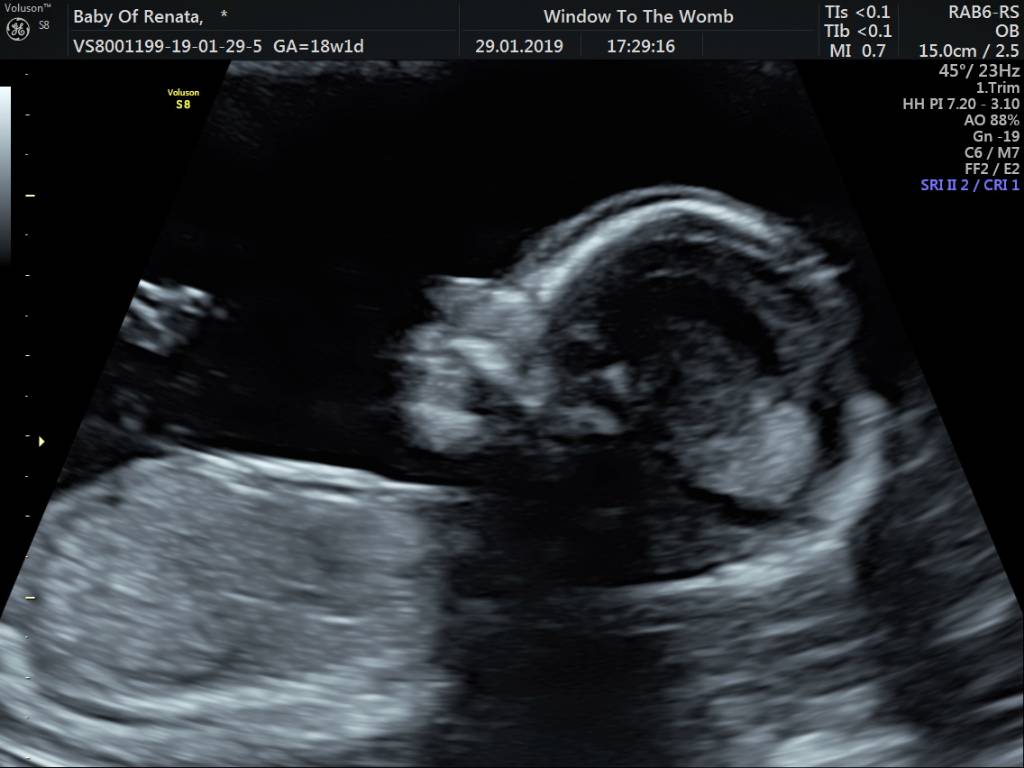

Jakoś się z czasem oswoiMy juz po. Na usg wszystko wyglada dobrze, nie widac zadnej przyczyny plamien. Serce mocne no i bedzie chlopak. Julka poplakala sie i zaczela spazmowac, ze chciala siostre.

Zobacz załącznik 938171